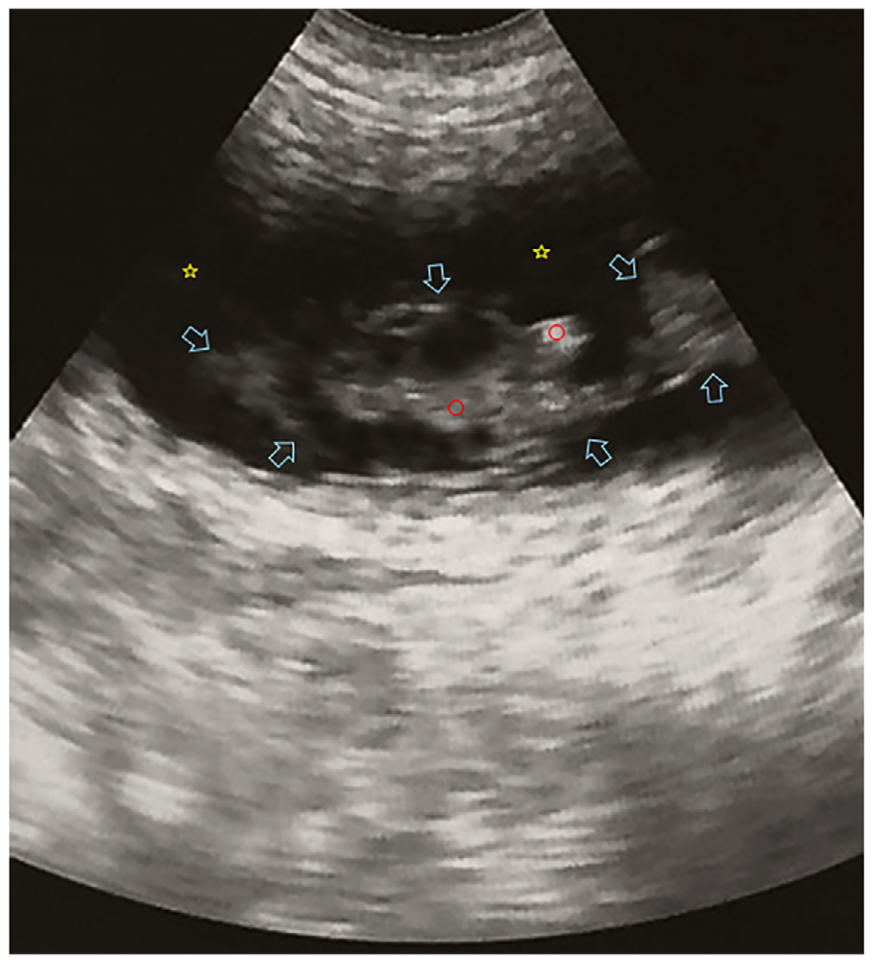

超声显示胎儿已无生命迹象,表现为胎儿无活动且无法检测到心跳(下图)。这些发现还得到了胎儿多普勒胎心监测仪的支持,该仪器显示胎儿的心跳频率与母猫的心率相比没有显著差异。未进行激素检测。

↑ 经腹超声显示胎儿成分(蓝色箭头)。类似胎儿骨骼的明亮回声结构(红色圆圈)和类似胎儿及子宫液体的低回声区域(黄色星)。